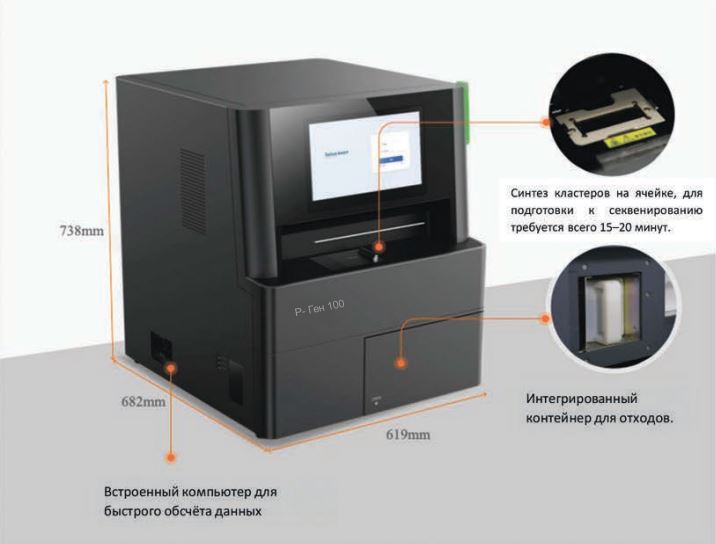

Генетический секвенатор Р-Ген 100

Основные особенности.

Простая в использовании платформа

- Набор реактивов включает всё необходимое для запуска и промывки;

- Автоматическая промывка после запуска.